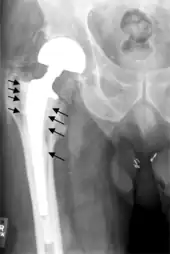

Fracture

Intraoperative fractures may occur. After surgery, bones with internal fixation devices in situ are at risk of periprosthetic fractures at the end of the implant, an area of relative mechanical stress. Post-operative femoral fractures are graded by the Vancouver classification.

Loosening

On radiography, it is normal to see thin radiolucent areas of less than 2 mm around hip prosthesis components, or between a cement mantle and bone. These may indicate loosening of the prosthesis if they are new or changing, while areas greater than 2 mm may be harmless if they are stable.[31] The most important prognostic factors of cemented cups are absence of radiolucent lines in DeLee and Charnley zone I, as well as adequate cement mantle thickness.[32] In the first year after insertion of uncemented femoral stems, it is normal to have mild subsidence (less than 10 mm).[31] The direct anterior approach has been shown to itself be a risk factor for early femoral component loosening.[33][34][35]